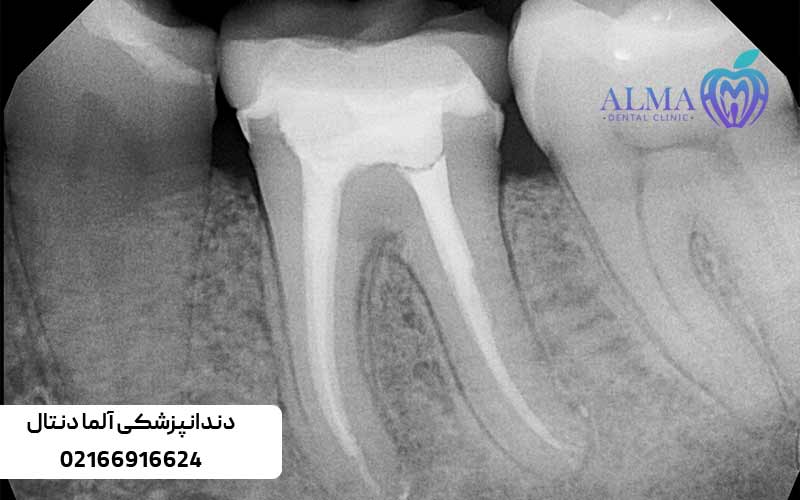

انواع ریشه دندان

تعداد زیادی از کانال های ریشه دندان وجود دارد ولی انواع مختلف ریشه دندان در چهار بخش تقسیم بندی می شود:

- تک ریشه : بییشتر در دندان های جلویی هستند.

- دو ریشه : برخی دندان های جلویی مانند کانین دارای این نوع ریشه هستند.

- سه ریشه : دندان های آسیابی مانند مولر سه ریشه دارند.

- چهار ریشه : برخی دندان های آسیابی دارای این نوع ریشه هستند.

تفاوت کانال و ریشه

هر دو ریشه و کانال از بخش های مهم دندان هستند اما باهم یکی نیستند، درواقع کانال جزئی از ریشه دندان است و با چشم قابل دیدن نیست حتی اگر بخشی از دندان خارج شده باشد.